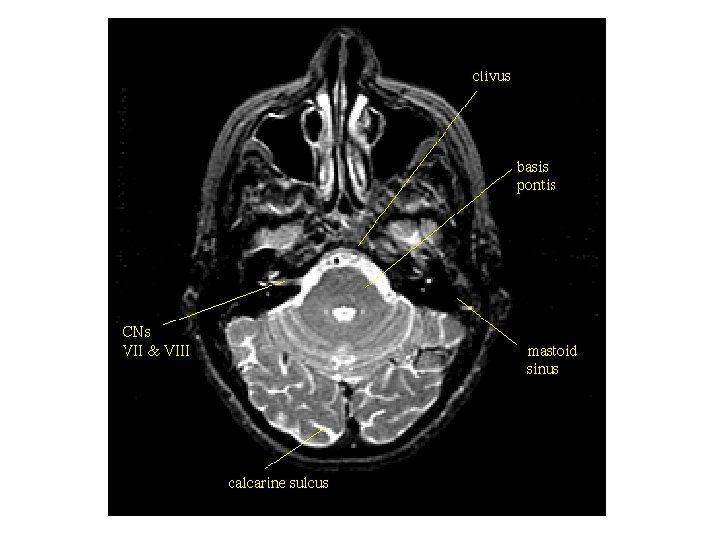

1. 송과체(pineal body) 2. 상구(superior colliculus) 3. 하구(inferior colliculus) 4. 하구완(brachium of inferior colliculus) 5. 대뇌각(cerebral peduncle) 6. 소뇌반구(cerebellar hemisphere) 7. 소뇌벌레(cerebellar vermis) 8. 교뇌(pons) 9. 제 4뇌실(4 th ventricle) 10. 빗장(obex) 11. 수뇌(myelencephalon) 12. 척수(spinal cord) Ⅴ. 삼차신경(trigeminal nerve) Ⅶ. 안면신경(facial nerve) Ⅷ. 전정달팽이신경(vestibulocochlear nerve)